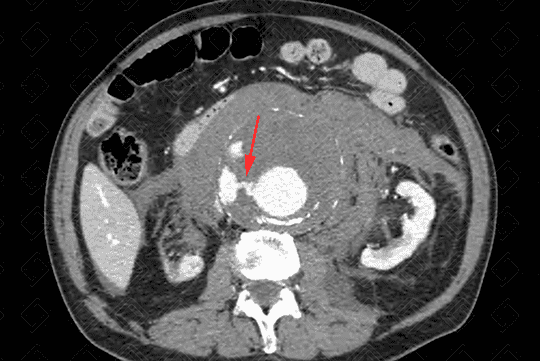

Texto alternativo para a imagem Figura 4. Créditos: Athena Hub/Medical Harbour

Descrição da figura 4: Tomografia computadorizada do abdome sem contraste (idealmente para avaliação vascular, estudo deve ser realizado com contraste) evidenciando dilatação aneurismática da aorta no seu segmento infrarrenal, medindo cerca de 3,3 cm (seta vermelha).